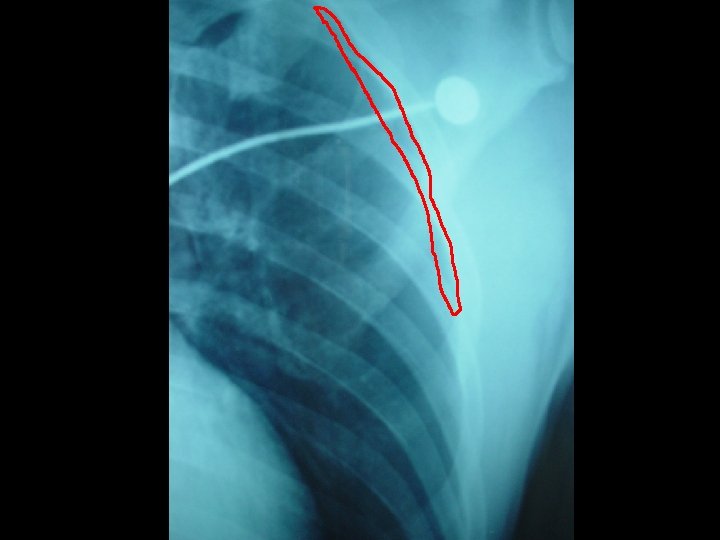

Dx: decompression sickness bilateral chest drain inserted Bilateral myringotomies performed 1 st session of recompression Urgent contrast swallow: no definite leakage in thoracic region

2 nd, 3 rd and 4 th session recompression on D 2, D 3 and D 4 respectively Persistent RUL monoparesis CT brain: hypodensity over L frontaloccipital lobe ? recent infarct MRI brain: acute infarct over L frontoparietal region Dx: deompression illness with pneumothorax, pneumoperitoneum and cerebral air embolism